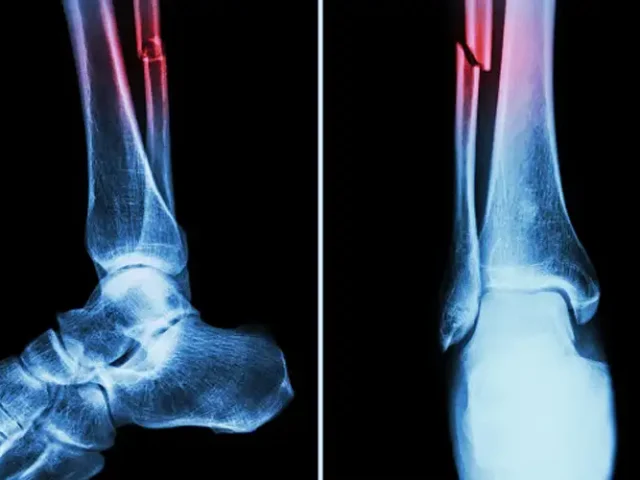

درمان شکستگی‌ها و دررفتگی‌ها

شامل بی‌حرکت‌سازی، جااندازی و در موارد شدید جراحی  است. هدف ترمیم استخوان و بازیابی عملکرد مفصل است.